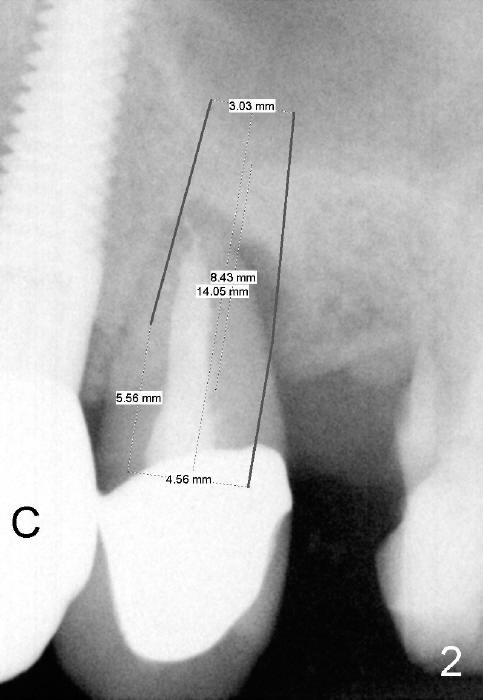

As soon as the tooth #12 is extracted and replaced with immediate implant, the patient feels that pain shifts to the tooth #13 (Fig.1 taken 3 months post implantation of #12; *: abutment).  By the 7th months postop (Fig.2 C: crown), the patient agrees to have a 2nd implant for the tooth #13.  Thorough debridement of the socket is planned.  Sinus lift is expected.  Take preop PA and photos.

To place bone graft efficiently, prepare 4 small pieces of gauze in a dap pen dish.  Dissolve Clindamycin with 2% Xylocaine (or 4% Septocaine) with 1:50,000 Epinephrine.  Use 3 pieces of gauze as usual, followed by normal saline irrigation.  Thoroughly debride the socket, since there is a fistula buccodistally.  Finish sinus lift and bone expansion/condensation with RT2,3, followed by 4.5x17 mm tap at the depth 14 mm.  The first intraop PA is taken.  If the bone is dense, use a 2 mm pilot drill to start osteotomy.

Use the last piece of the gauze for hemostasis before bone grafting.  Wet the bone graft lightly with blood squeezed from the last gauze.  Squeeze extra blood out of the bone graft inside the plastic dap pen dish with dry 2x2 and suction tip.  Do it as quick as possible so that hemorrhage does not recur before bone grafting.  Use 2.5 or 3.0 mm Bicon flat end osteotome to push bone graft into the sinus.  A 4.5 or 5x14 mm tapered implant is to be used.